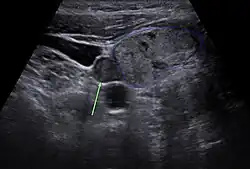

Vor einer geplanten Operation können Lokalisation und Größe der betroffenen Nebenschilddrüsenkörperchen durch Sonografie, Szintigrafie mit Technetium-99m-Sestamibi (Nebenschilddrüsenszintigrafie), Computertomographie oder Kernspintomografie dargestellt werden.

Nebenschilddrüse in der Sonographie -

Die Sensitivität dieser diagnostischen Verfahren ist jedoch begrenzt. Besonders bei komplizierteren Fällen, wie zum Beispiel bei Vorhandensein von mehreren auffälligen Nebenschilddrüsen oder entfernt auftretenden Nebenschilddrüsenadenomen, kann eine zuverlässige Lokalisation aller betroffenen Epithelkörperchen schwierig sein.[60] Neuere bildgebende Verfahren, wie Positronenemissionstomographie (PET) mit speziellen Radiopharmaka wie 68Ga-Trivehexin, können in solchen Fällen eine zuverlässigere Lokalisation ermöglichen,[61] wodurch deren komplette chirurgische Entfernung und damit eine vollständige Heilung des primären Hyperparathyreoidismus wahrscheinlicher wird.